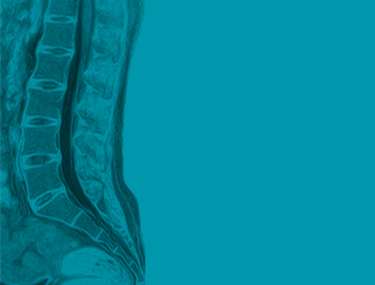

Definition: Im Unterschied zum konventionellen Röntgen arbeitet die Kernspintomographie mit starken Magnetfeldern, weswegen mit dieser Methode andere Strukturen als im herkömmlichen Röntgenbild sichtbar gemacht werden können. Gerade auch im Bereich der Sportmedizin ist deswegen diese Methode inzwischen zum unverzichtbaren Standard bei der Abklärung von Sportverletzungen geworden.

Das MR liefert auch bildgebende Information über Weichteile. Gerade im Gelenksbereich werden neben dem knöchernen Skelett auch Strukturen wie Bandapparat, Sehnen, Gelenkskapsel, Knorpel, Meniscus, Muskel bildhaft in mehreren Ebenen abgebildet. Ebenso können bei Unfällen verletzungsbedingte Flüssigkeitsansammlungen wie bei Gelenkserguss und Schwellung durch Einblutung im Weichteilmantel dargestellt werden. Ein Quantensprung in der prezisen Findung einer Diagnose – damit wird bei Verletzungen im Gelenksbereich das MRI zum Goldstandard in der Sportmedizin.